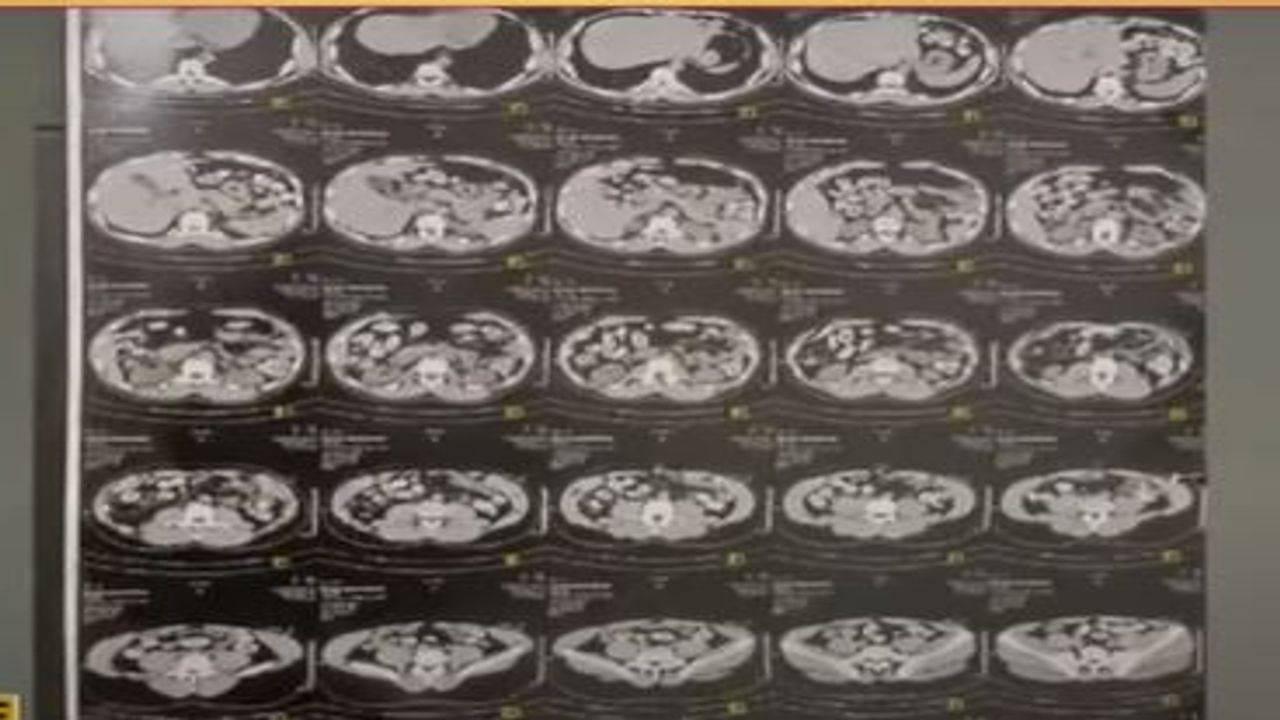

દક્ષિણ આફ્રિકા (South Africa)ના યુગાન્ડાથી અમદાવાદ (Ahmedabad) આવેલા યુવક-યુવતીના શરીરમાંથી કાઢેલી 165 કેપ્સ્યૂલ (Capsules)માં 1.8 કિલો હેરોઇન મળ્યું છે. સીટી સ્કેનમાં બંનેના પેટમાં કેપ્સ્યૂલ દેખાઈ હતી. જેને સોલા સિવિલમાં એનિમા આપીને કાઢી લેવાઈ હતી.

સીટી સ્કેનમાં દેખાઇ હતી શંકાસ્પદ કેપ્સ્યૂલ

કેન્દ્ર સરકારના ડાયરેક્ટોરેટ ઓેફ રેવન્યુ ઇન્ટેલિજન્સ વિભાગને બાતમી મળી હતી કે સાઉથ આફ્રિકામાંથી આવેલા યુવક-યુવતીના પેટમાં ડ્રગ્સની કેપ્સ્યુલ છે. જે બાદ ત્રણ દિવસ પહેલા સાઉથ આફ્રિકાથી અમદાવાદ આવેલા યુવક યુવતીની તેમણે ધરપકડ કરી હતી. આ યુવક-યુવતીને સોલા સિવિલમાં દાખલ કરાયા હતા.

તબીબો દ્વારા પહેલાં યુવક યુવતીના એક્સરે અને બાદમાં સીટી સ્કેન કરાયા હતા. જેમાં શંકાસ્પદ કેપ્સ્યુલ દેખાઇ હતી. બંનેને એનિમા આપીને 135 શંકાસ્પદ ડ્રગ્સની કેપ્સ્યૂલ કાઢવામાં આવી હતી. બન્ને યુગાન્ડાના નાગરિકોના શરીરમાંથી 165 જેટલી કેપ્સ્યૂલમાંથી 1.811 કિલો હેરોઇન ડ્રગ્સ મળી આવ્યું હતું. બંનેની NDPS એક્ટ 1985 હેઠળ ધરપકડ કરવામાં આવી હતી.